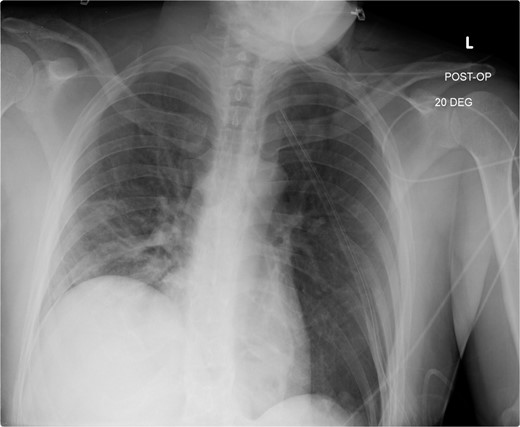

This is a case of a 26-year-old male patient who presented with symptoms of dyspnea on exertion, left chest pressure, and constipation for 7 years. He was a never smoker with no history of trauma, nor prior neck and chest surgeries. Baseline pulmonary functions tests revealed FEV1 of 71% predicted and DLCO of 77% predicted. Work-up included a computed tomography (CT) of the chest which revealed marked left hemidiaphragm elevation with compression atelectasis of the left lower lobe (Fig. 1). A fluoroscopic sniff test showed paradoxical movement of the left hemidiaphragm consistent with diaphragmatic paralysis. Interestingly, abdominal imaging obtained 14 months before surgery showed a displaced stomach but without volvulus (Fig. 2). Due to the impact on the patient’s quality of life, he was offered surgical treatment with a robotic-assisted left thoracoscopic plication of the diaphragm. This was done using a three-arm technique using the Da Vinci Xi surgical system (Intuitive Surgical, Sunnyvale, CA) with an additional assistant port. Plication was performed by placing multiple horizontal mattresses sutures reinforced with pledgets in an anterior–posterior orientation, and systematically working medial to lateral. A postoperative chest X-ray showed a satisfactory result (Fig. 3).

Immediate post-operative film demonstrates intact repair, and well-positioned chest-tube.

Following chest-tube removal, a film was taken, revealing even hemi-diaphragms, which was notably higher than immediate post-operatively, but within normal limits.